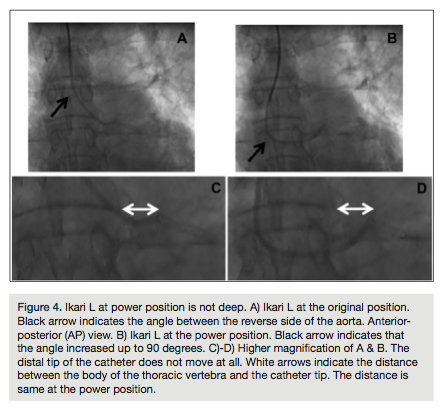

Occasionally, a stronger backup force is necessary for an extremely complex lesion. There is an easy method of manipulation to increase backup force in the Ikari L. This technique is as easy as

pushing the guiding catheter up to the reverse side angle of 90 degrees (Figure 4). At this point, the backup force becomes much more significant. Deep engagement of the Judkins L also generates greater backup force; however, this can sometimes damage the left main. However, the power position with the Ikari L is safe, because the distal tip is never inserted deeply due to its differentiated design. To date, no left main dissections with Ikari L have been reported in our database (>1000 cases) and in the reports from Youssef et al (>600 cases)5, or other studies6.

What is the benefit of the Ikari L type guide catheter? Engagement is just as easy as with the traditional Judkins L. When a strong backup force is necessary, you can make a power position that is directly within the operator’s control. One may have concern about coronary dissection at the power position. However, our observations on many cases show that the power position of the Ikari L is not a deep insertion of the catheter. The distal tip does not move with this maneuver, because of its sophisticated design. Even at the power position, the catheter tip of the Ikari L is still outside the original position of the EBU/XB-type catheters. No left main dissection caused by an Ikari L has been reported in our database (>1000 cases) and in the reports from Youssef et al (>600 cases)5. Thus, we find the Ikari L to be very easy and most of all, very safe.